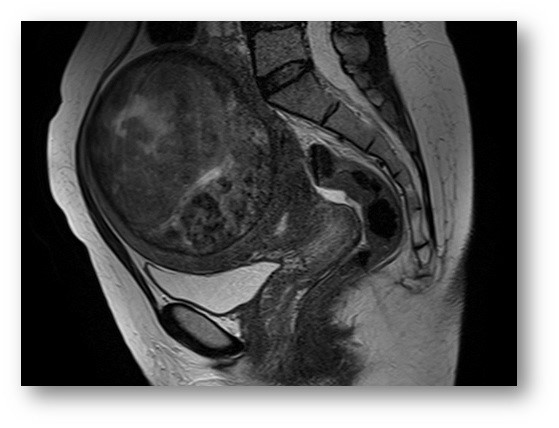

КТ диагностика тубоовариального абсцесса: Подходы и изображения

Раздел: Объективный взгляд